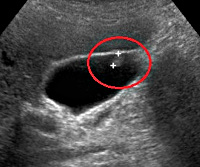

D37.6 Neoplasm of uncertain or unknown behaviour, liver, gallbladder and bile ducts